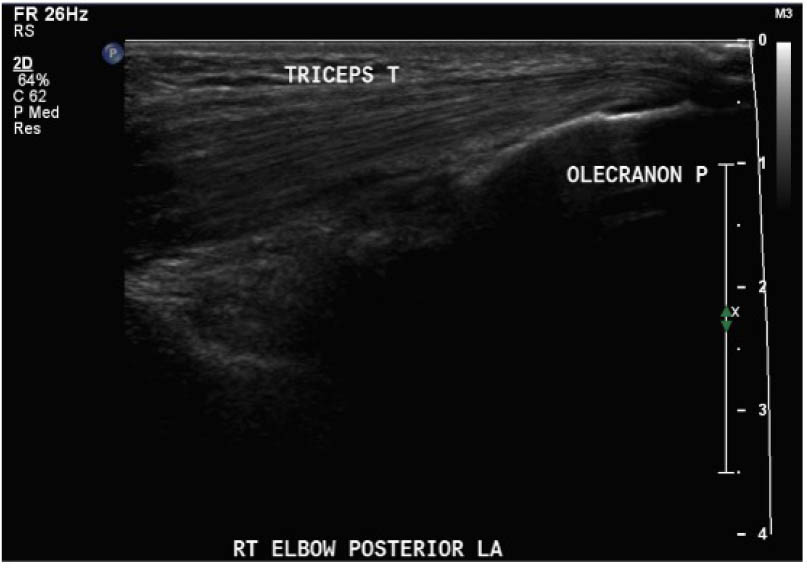

The study procedure consisted of a POCUS performed by a physiotherapist and a sonographer. The POCUS scanning procedure is presented in Appendix 1. The POCUS scans were performed in the haemophilia ambulatory clinic at patient presentation, one-week follow up, and two-week follow-up. The order of assessment was based on clinician availability. The sonographer was allowed to add additional images to the imaging protocol given their area of expertise, but the physiotherapist was instructed to acquire the images according to the scanning procedure. Ambiguous results were referred to the diagnostic imaging department for further formal investigation. Both the physiotherapist and the sonographer were blinded to each other's findings and to the results of previous scans. Methods of blinding included the use of a private clinic room and each clinician performing their assessment and documentation independently. Case report forms were placed in a sealed envelope. POCUS images were saved on the hard drive of the POCUS machine (GE Logiq) using an anonymous participant identification number.

Outcomes were assessed at presentation, one-week follow-up, and two-week follow up, resulting in a three-week study period. For the primary objective, the outcome of interest was the binary decision on the presence or absence of blood within the joint. As the technique and protocol in this study was specific to haemophilia, the criteria used to distinguish blood from effusion on ultrasound was blood presents as a complex fluid collection with mixed echogenicity and displaceable speckles on real time compression and effusion presents as simple anechoic fluid with the absence of echoes [35]. In the context of haemophilia with no symptoms suggestive of infection, complex effusions with mixed echogenicity can be assumed to represent haemarthrosis based on previous studies that have documented the accuracy of this approach using joint aspiration [35]. The physiotherapist completed the scanning protocol and interpreted the findings to make the binary assessment. Since interpreting ultrasound falls outside the scope of the sonographer, the sonographer provided an impression on the presence or absence of blood on the case report form. The radiologist read the sonographer images and provided a final diagnosis. The radiologist also reviewed the images of the physiotherapist performed ultrasound. To compare the level of agreement, the radiologist's final diagnosis was compared to the physiotherapist's interpretation. Both the physiotherapist and the sonographer recorded inconclusive ultrasound findings as absence of blood within the joint.

For the secondary objective, criteria used to evaluate image quality were appropriate pre-sets, depth, field of view, focus, gains/time gain compensation, colour and/or power Doppler, with suitable landmarks and annotation. Image quality was evaluated by the radiologist post hoc and rated as optimal, acceptable, or sub-optimal. Optimal was defined as good image quality with optimal ultrasound settings and correct annotation/documentation. Acceptable was defined as good image quality, with one image setting that should have been better optimized or a minor error in annotation/documentation that did not impact the interpretation of the POCUS scan. Sub-optimal was defined as poor image quality with more than one image setting not sufficiently optimised or an error in annotation/documentation that impacted the radiologists’ interpretation of the POCUS scan.

Post hoc analysis of the quality of the ultrasound images is shown in Table 2. The physiotherapist-performed POCUS scans demonstrated that 84.6% of the images were rated by the radiologist as optimal, 15.4% were rated as acceptable, and none were rated as sub-optimal. For the sonographer-performed POCUS scans, 88.9% of the images were rated as optimal, 11.1% were rated as acceptable, and none of the scans were rated as sub-optimal.